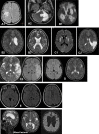

Cerebral palsy (CP) is one of the most frequent causes of motor disability in children. According to the up-to-date definition, CP is a group of permanent disorders of the development of movement and posture, causing activity limitations that are attributed to non-progressive disturbances that occurred in the developing foetal or infant brain. The CP definition has evolved over time; the problem is aetiologically and clinically very heterogeneous. According to European data, the average frequency of CP is 2.08 per 1000 live births, but in the group of children born with a body weight below 1500 g, the frequency is 70 times higher when compared with the group of children with a body weight over 2500 g at birth. The risk factors for CP can be divided into pre-conception, prenatal, perinatal and postnatal ones. CP commonly co-exists with epilepsy, in particular drug-resistant epilepsy, but also with mental retardation, visual and hearing impairment, as well as feeding and behavioral disorders. The degree of motor problem varies from mild to very severe making the child totally dependent on caregivers. Cerebral palsy is divided into forms depending on the type of motor disorders which dominate the clinical presentation; the traditional classifications by Ingram and Hagberg have now been replaced by the Surveillance of Cerebral Palsy in Europe classification which divides CP into spastic, dyskinetic and ataxic forms. Although cerebral palsy is a clinical diagnosis, modern diagnostic imaging provides information that allows the division of the results of magnetic resonance imaging in children with cerebral palsy into five groups according to the magnetic resonance imaging classification system. Just as the clinical presentation and the factors predisposing for CP are very diverse, treatment is also a very complex problem. Modern treatment of spasticity includes both botulinum toxin therapies and surgical techniques, eg, rhizotomy. The authors present current views on definitions, risk factors, diagnostics and treatment of CP as well as comorbid problems, eg, drug-resistant epilepsy.